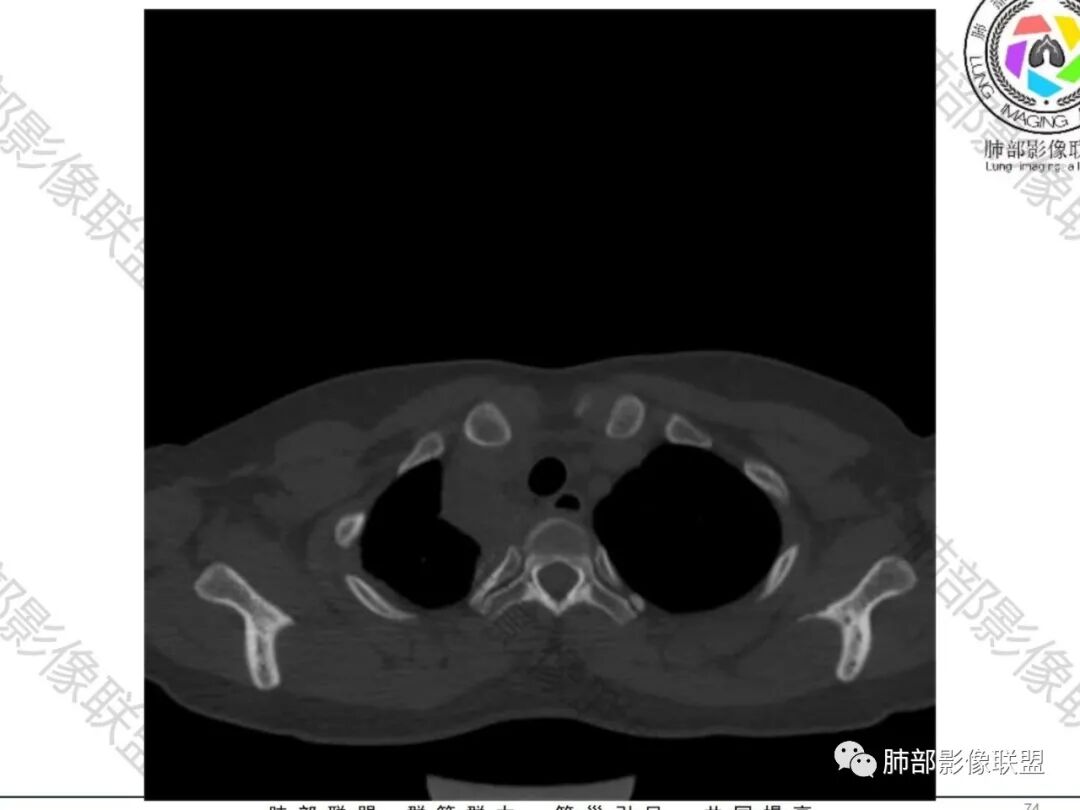

一切∮随缘:双侧胸廓塌陷,以右侧为主,右侧肋间隙狭窄,双肺上叶及右肺下叶胸膜下多发不规则肿块,密度不均匀,内部可见条片状,不规则钙化影,部分钙化不密实,双肺多发纤维索条影,似陈旧性病灶,双侧胸水,临床年轻女性,无感染症状,考虑考虑结核淀粉样变,转移性钙化,弥漫性肺骨化病。

王秀仙:双肺多发条索状及结节状病灶,部分钙化,边界清晰,双侧纵膈胸膜及双侧胸膜可见结块状及弧形软组织肿块,内见多发钙化灶,右侧胸腔塌陷,考虑结核伴淀粉样变性。鉴别胸膜间皮瘤。

丽:双肺散在索条及条片状高密度影,边界清晰,部分实变内可见钙化,支气管管壁增厚,双肺胸膜局限性增厚伴钙化,部分肋骨密度增高,首先考虑结核并淀粉样变性,鉴别转移性钙化,肿瘤样钙质沉着症,胸膜间皮瘤。

这个骨窗很有价值

价值就在于这个密度

骨质破坏,但是密度增高

你对比一下髓腔

它这个髓腔密度不对,皮质也欠连续,还是以骨头为主

南边:那就是说这个肋骨是自身的病变,有成骨性骨质破坏